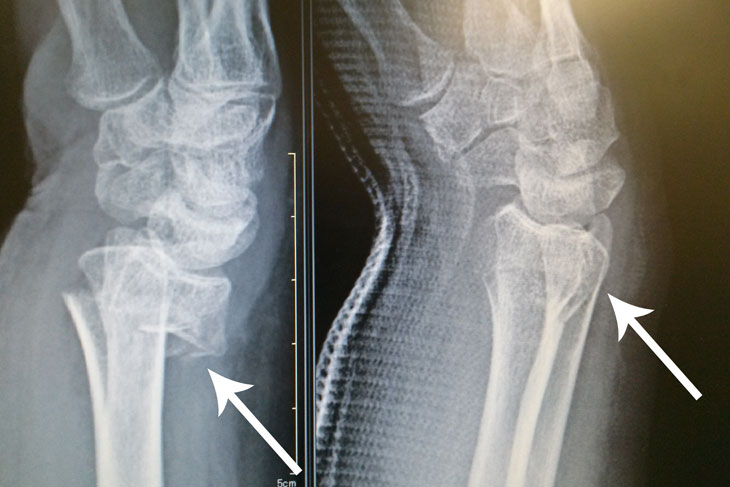

動画は、当時行った手首骨折整復の様子です。

実際の整復前後のレントゲン画像です。

整復後のレントゲンでは、骨の位置と長さが適切に回復していることがはっきりと示されています。